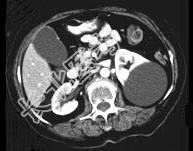

- 多项选择题女,38岁, 左腰部胀痛不适,CT平扫+增强如图所示, 下列说法正确的是 ( )

A、平扫时可见左肾一类圆形囊性病灶

B、病灶边界清晰,表面光整

C、增强扫描皮质期和实质期该病灶均未见强化

D、考虑为左肾囊性肾癌

E、考虑为左肾囊肿